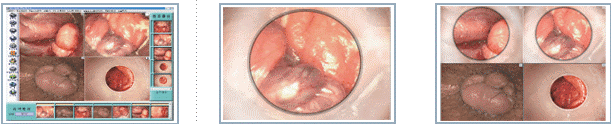

Ректороманоскопия кишечника позволяет врачу-проктологу визуально оценить внутреннее состояние слизистой кишечника на глубине 25-35 см. При применении увеличивающей оптики можно рассмотреть мельчайшие изменения слизистой оболочки, а проведенная видеорегистрация обследования позволяет со 100%-й точностью установить диагноз. В ходе манипуляций врач-проктолог видит цвет слизистой, кровеносные сосуды, диаметр просвета кишки, а также наличие на ее стенке геморроидальных узлов, трещин, рубцов, полипов и опухолей.

В Центре современных медицинских технологий «АКВА МЕД МАРИН» видеоректороманоскопия проводится с помощью единственной в городе медицинской диагностической оптической видеосистемы Dr. CamscopeDCS-103R (видеоректоскоп), которая позволяет получить на мониторе цветное качественное изображение с высоким разрешением для проведения точной и достоверной диагностики в колопроктологии. Дает возможность врачу и пациенту увидеть видеоизображение области заболевания до и после лечения, детально увидеть изменения формы и цвета тканей, функциональные и структурные изменения. Видеоректоскоп значительно облегчает проведение различных хирургических манипуляций, биопсию тканей.